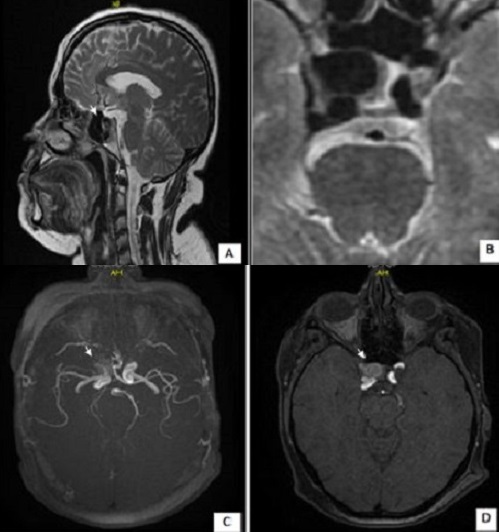

The aneurysm is a dilation of an artery focused secondary to a parietal structural modification. The intracranial carotid aneurysm is a rare disease, which exposes to serious risks, we report a case. A 46-year-old women, followed for infertility last 5 years, which presents a secondary amenorrhea 6 months ago, without functional signs of anterior pituitary deficiency or signs of intracranial hypertension or galactorrhea. hormonal analysis shows hyperprolactinemia to 97 ng/ml. Hypothalamic-pituitary magnetic resonance imaging (MRI) shows a round formation, intra and latero sellar right hypointense in T1 and T2 (17 * 12mm) with contrast enhancement after injection (A), it is in intimate contact with right carotid cavernous and lifting the head of a right optic chiasm and compression at the bottom of the cavernous sinus (B). The magnetic resonance angiography is in favor of an unruptured aneurysm carotid (C, D). The carotid aneurysm is a diagnosis that is rare, usually asymptomatic and discovered during a major complication (break), it should be mentioned in the evocative radiological appearance. Screening can be organized and magnetic resonance angiography is therfore the first line examination. The arteriography is the key examination that allows the diagnosis and endovascular treatment. Good technical knowledge of these imaging methods, artifacts and pitfalls images allow reliable detection of intracranial aneurysms and performing an accurate account to be provided to clinicians. We insist, through this observation, on the interest not to disregard this diagnosis.